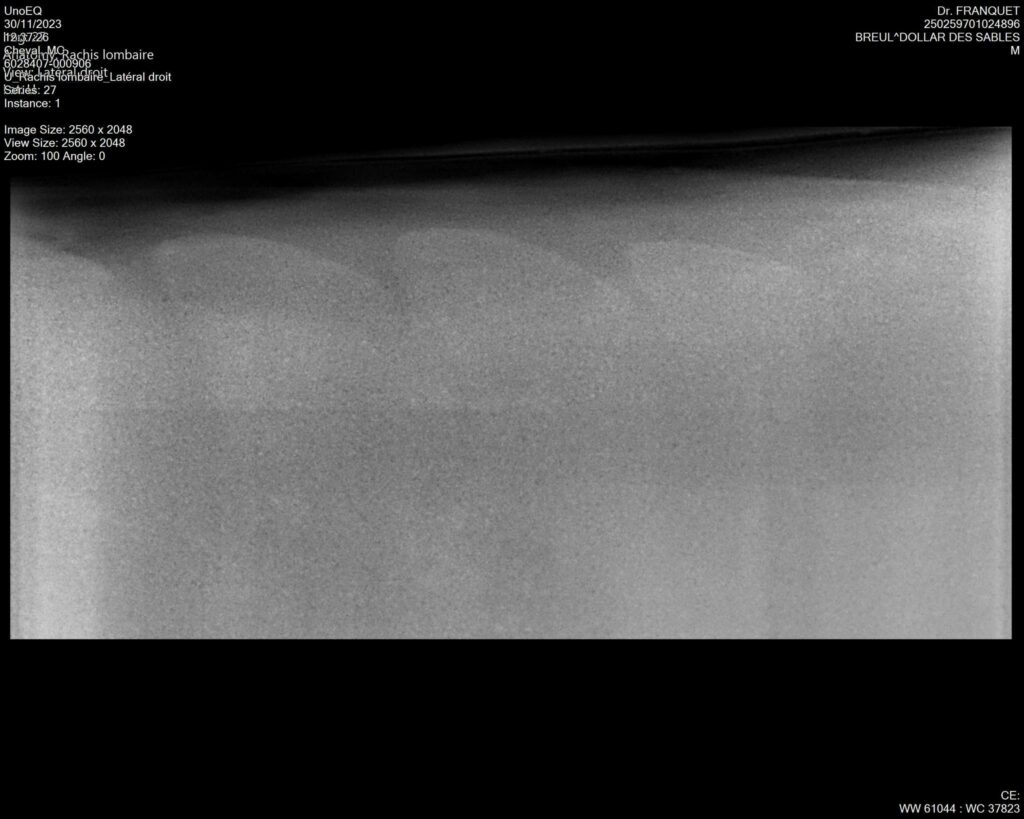

DOLLAR DES SABLES, Selle Français, hongre, 12 ans par DOLLAR DE MURIER x ABKE (ACORADO). Classé 135 avec professionnel à fait 125 avec amateur, récemment classé sur amateur 1GP 120. Très beau modèle ! Gentil cheval, respectueux avec des moyens et du sang. Transport OK, maréchalerie OK, santé RAS, Bilan clichés radios OK.

RADIOS